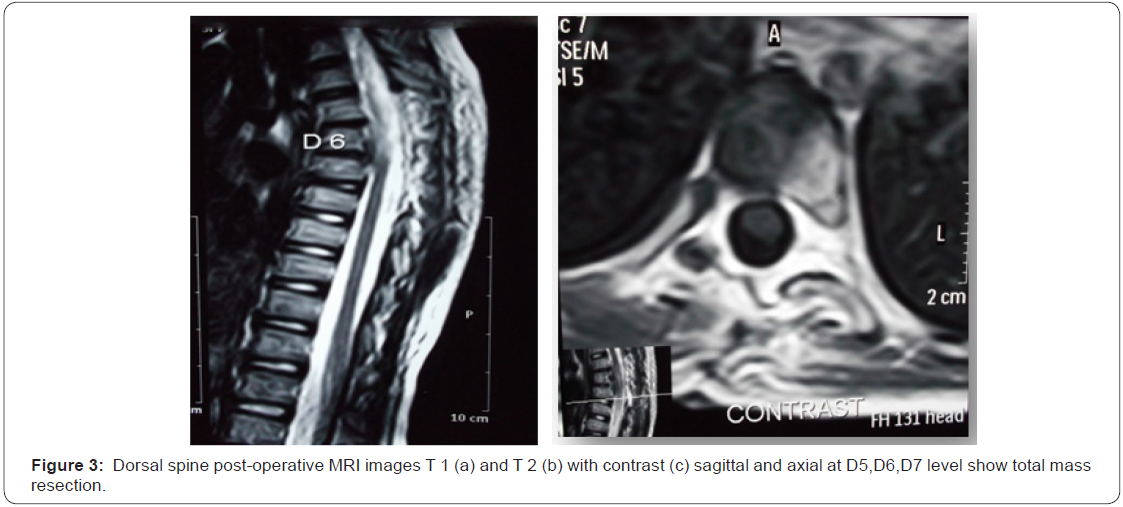

OAJNN.MS.ID.555659